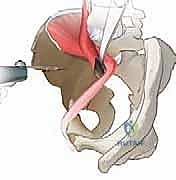

الخطوة الرابعة: إعادة التوجيه (Reorientation)

بعد تحرير التجويف، يقوم الدكتور هطيف بتدويره في ثلاثة أبعاد (3D) ليغطي رأس عظمة الفخذ بشكل مثالي. يتم التحقق من التغطية الجديدة باستخدام جهاز الأشعة السينية الفلوروسكوبي داخل غرفة العمليات لضمان الزوايا المثالية.